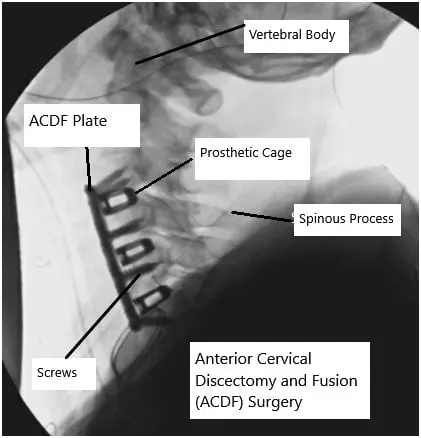

Anterior cervical discectomy and fusion (ACDF) is one of the most commonly performed neck surgeries. The ACDF surgery is done to relieve symptoms associated with compression of the spinal cord or the spinal nerves in the cervical region. The recovery after ACDF surgery may vary from patient to patient due to different baseline health and the type of ACDF surgery performed,

The ACDF helps to relieve symptoms such as neck pain, numbness and tingling in the arms, shoulders, or hand, shooting pain in the arms, weakness of hands, or lower extremities. During the surgery, the spine surgeon accesses the cervical vertebrae from the front of the neck.

The surgeon removes the diseased intervertebral disc and any tissues that compress the neural structures. A bone graft is usually placed along with a prosthetic bone cage to maintain the disc space and help in the union.

X-ray showing ACDF surgery.